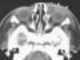

Dacryocystitis

Dacryocystitis is an infection of the lacrimal sac, secondary to obstruction of the nasolacrimal duct at the junction of lacrimal sac. The term derives from the Greek dákryon (tear), cysta (sac), and -itis (inflammation). [Source: Wikipedia ]